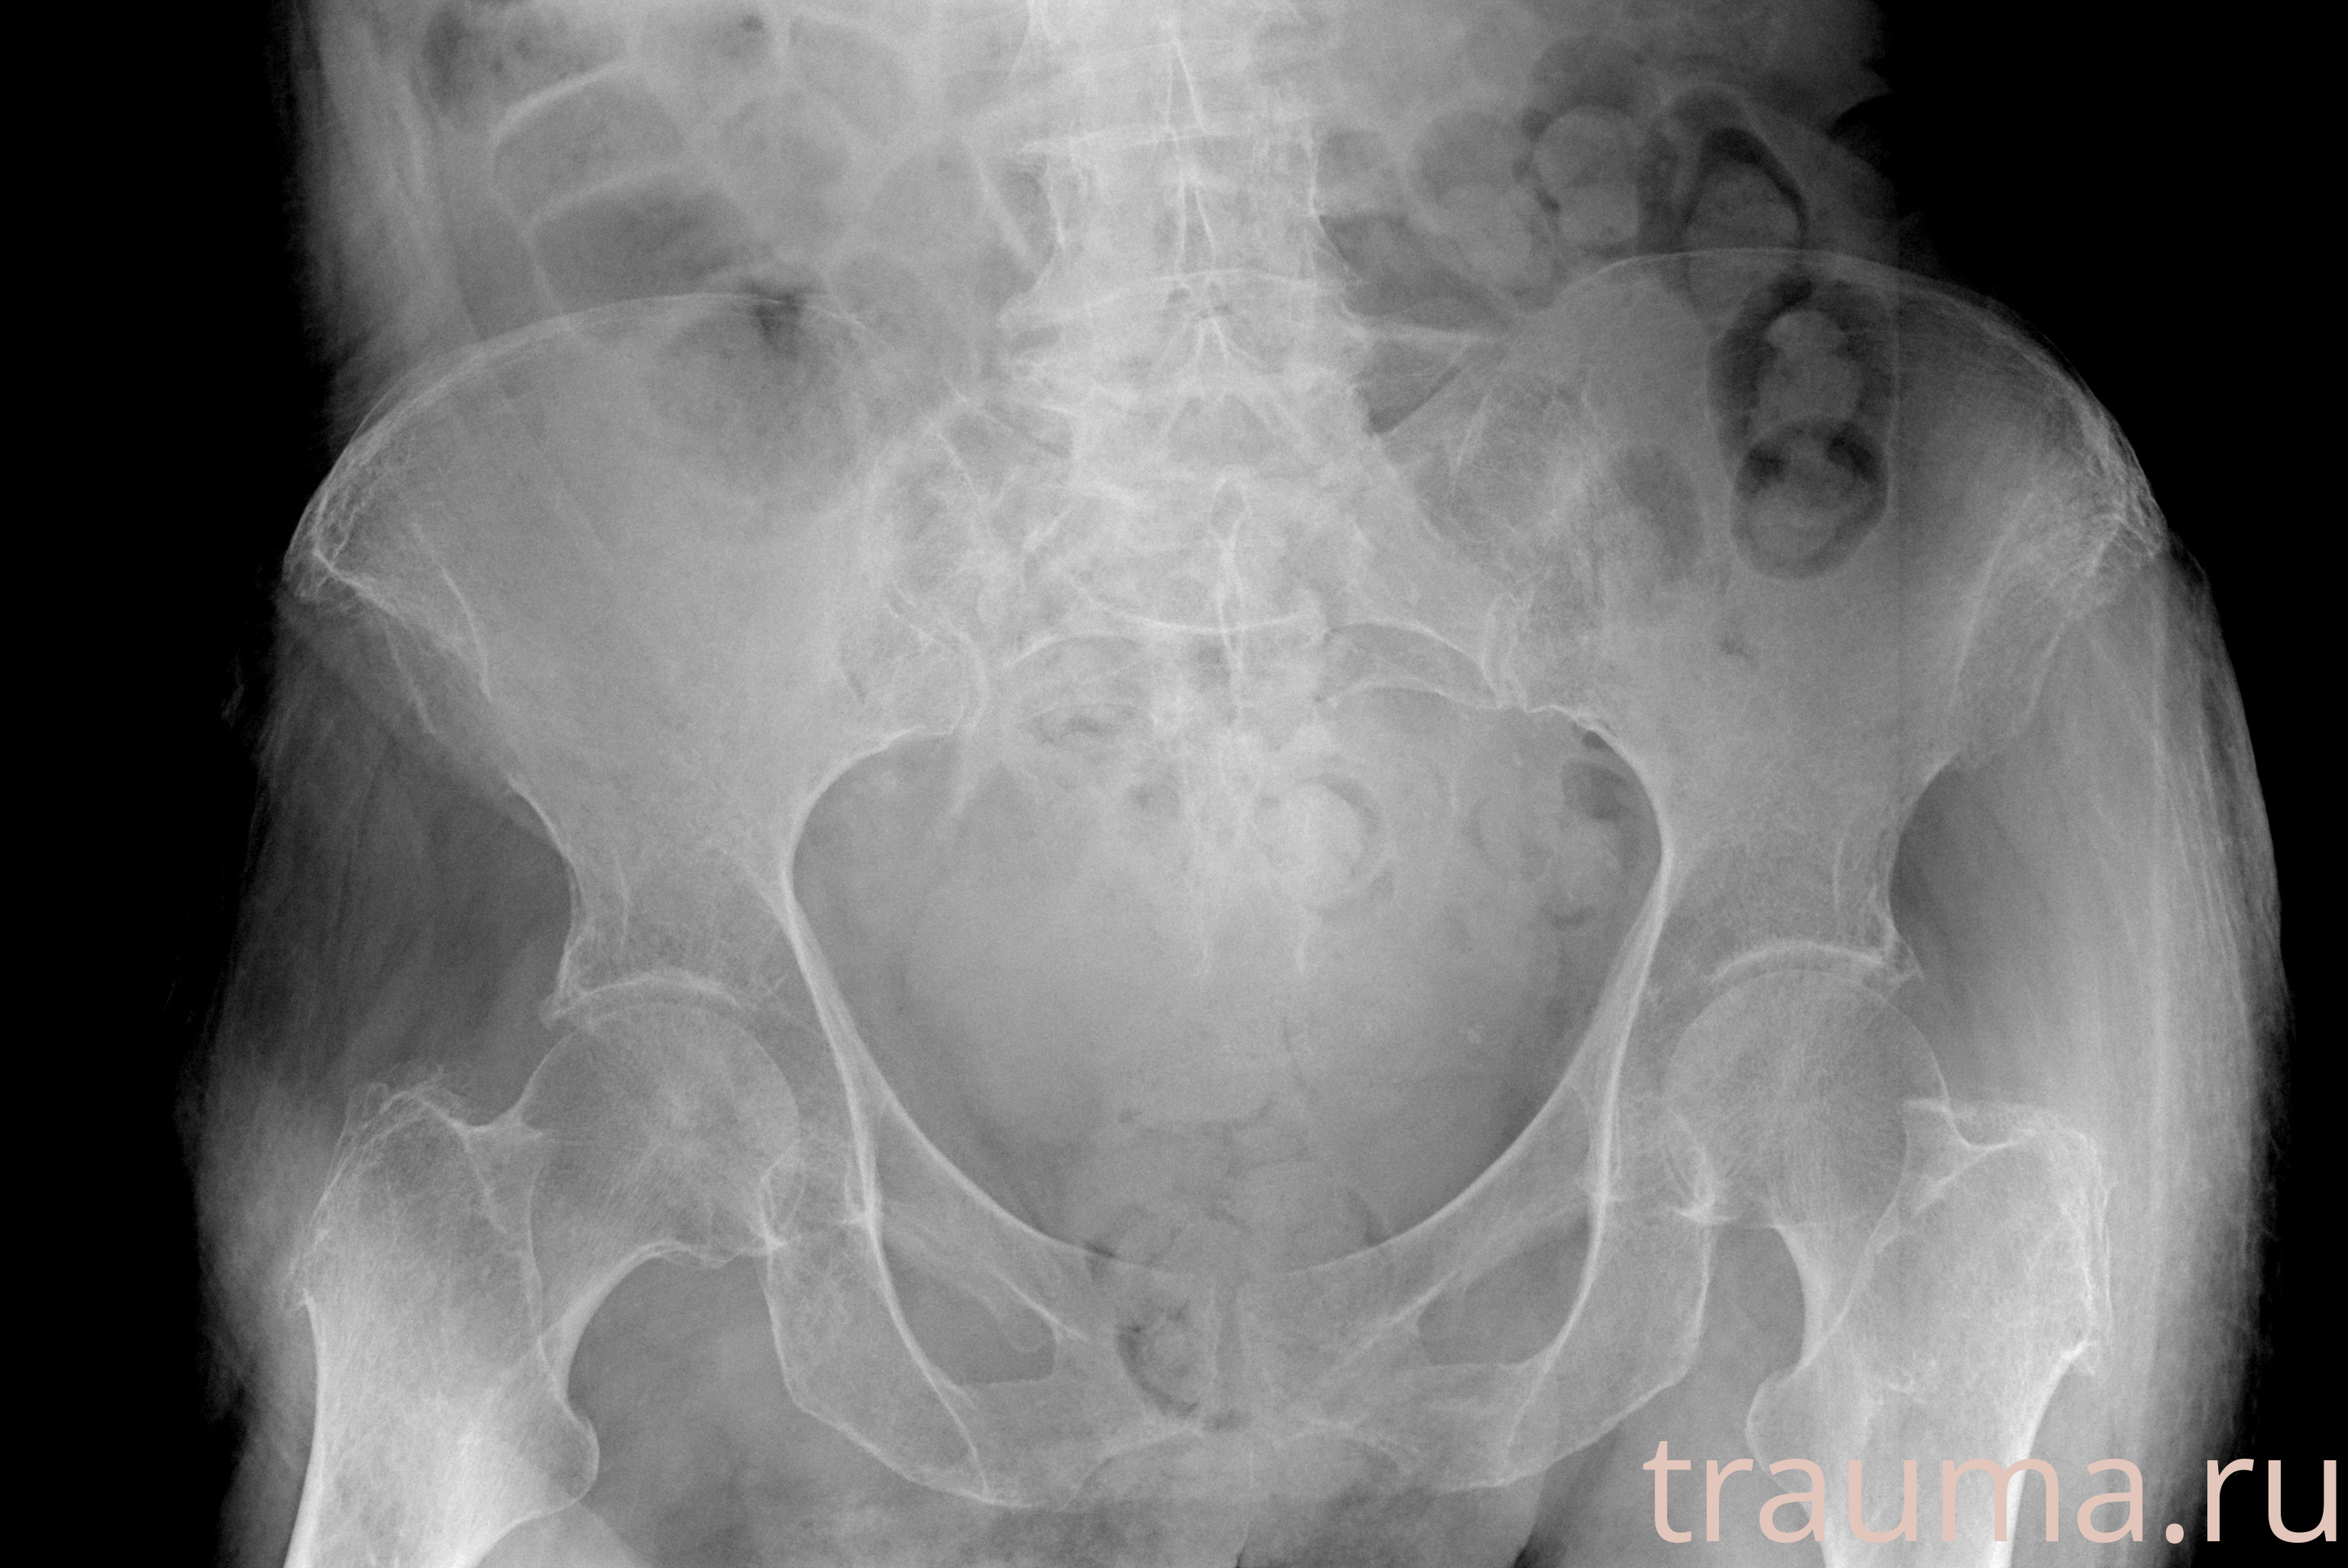

Рентгенограммы

Рентген на дому: по вашему адресу приезжает врач-рентгенолог, травматолог-ортопед с мобильным рентгеновским аппаратом, проводит диагностику травмы или заболевания, делает необходимые рентгенограммы, дает рекомендации по дальнейшему лечению. Получить качественные снимки в домашних условиях возможно благодаря уникальной методике, разработанной МосРентген Центром для института  Склифосовского

при переломе шейки бедра и пневмонии от компании МосРентген Центр - партнера Института имени Склифосовского